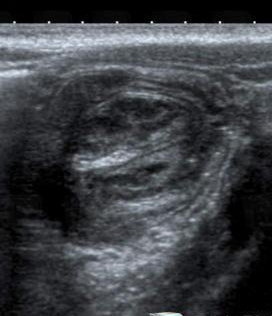

- Echographie

du tube digestif peu recherche d'une

epaissisement de la paroie du tractus digestif , une

masse intraparietal , lesions inflamatoires (

appendicite ) |

| Images echographiques de

appendice inflame en coupe transverse ( signe Halo)

et coupe longitudinal incline .** |

Appendicite aigue

en coupe tranverse et longitudinal . Echographies

|

Image echographique de

iinvagination ileo-coecal . Image en cocarde |